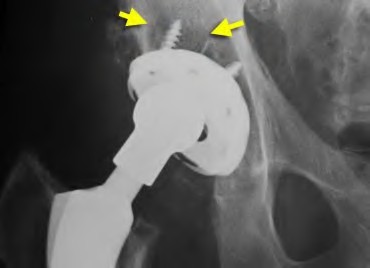

A 55-year-old highly active man is scheduled for a total hip arthroplasty (THA). The surgeon considers utilizing a ceramic-on-ceramic bearing surface to maximize longevity. Which of the following is the most notable disadvantage or complication specific to a ceramic-on-ceramic bearing compared to ceramic-on-highly cross-linked polyethylene?

Options:

- A significantly higher rate of volumetric wear debris generation

- An increased risk of profound macrophage-mediated osteolysis

- Audible squeaking during hip articulation

- Severe adverse local tissue reactions (ALTR) mediated by a Type IV hypersensitivity

- Accelerated corrosion at the femoral head-neck trunnion

Correct Answer: Audible squeaking during hip articulation

Explanation:

Ceramic-on-ceramic (CoC) bearings offer the lowest wear rates of all THA bearing couples and do not cause significant osteolysis or metal-related hypersensitivity. However, a well-documented unique complication of CoC bearings is audible squeaking during motion, occurring in up to 10-15% of patients in some series, often associated with micro-separation or impingement.